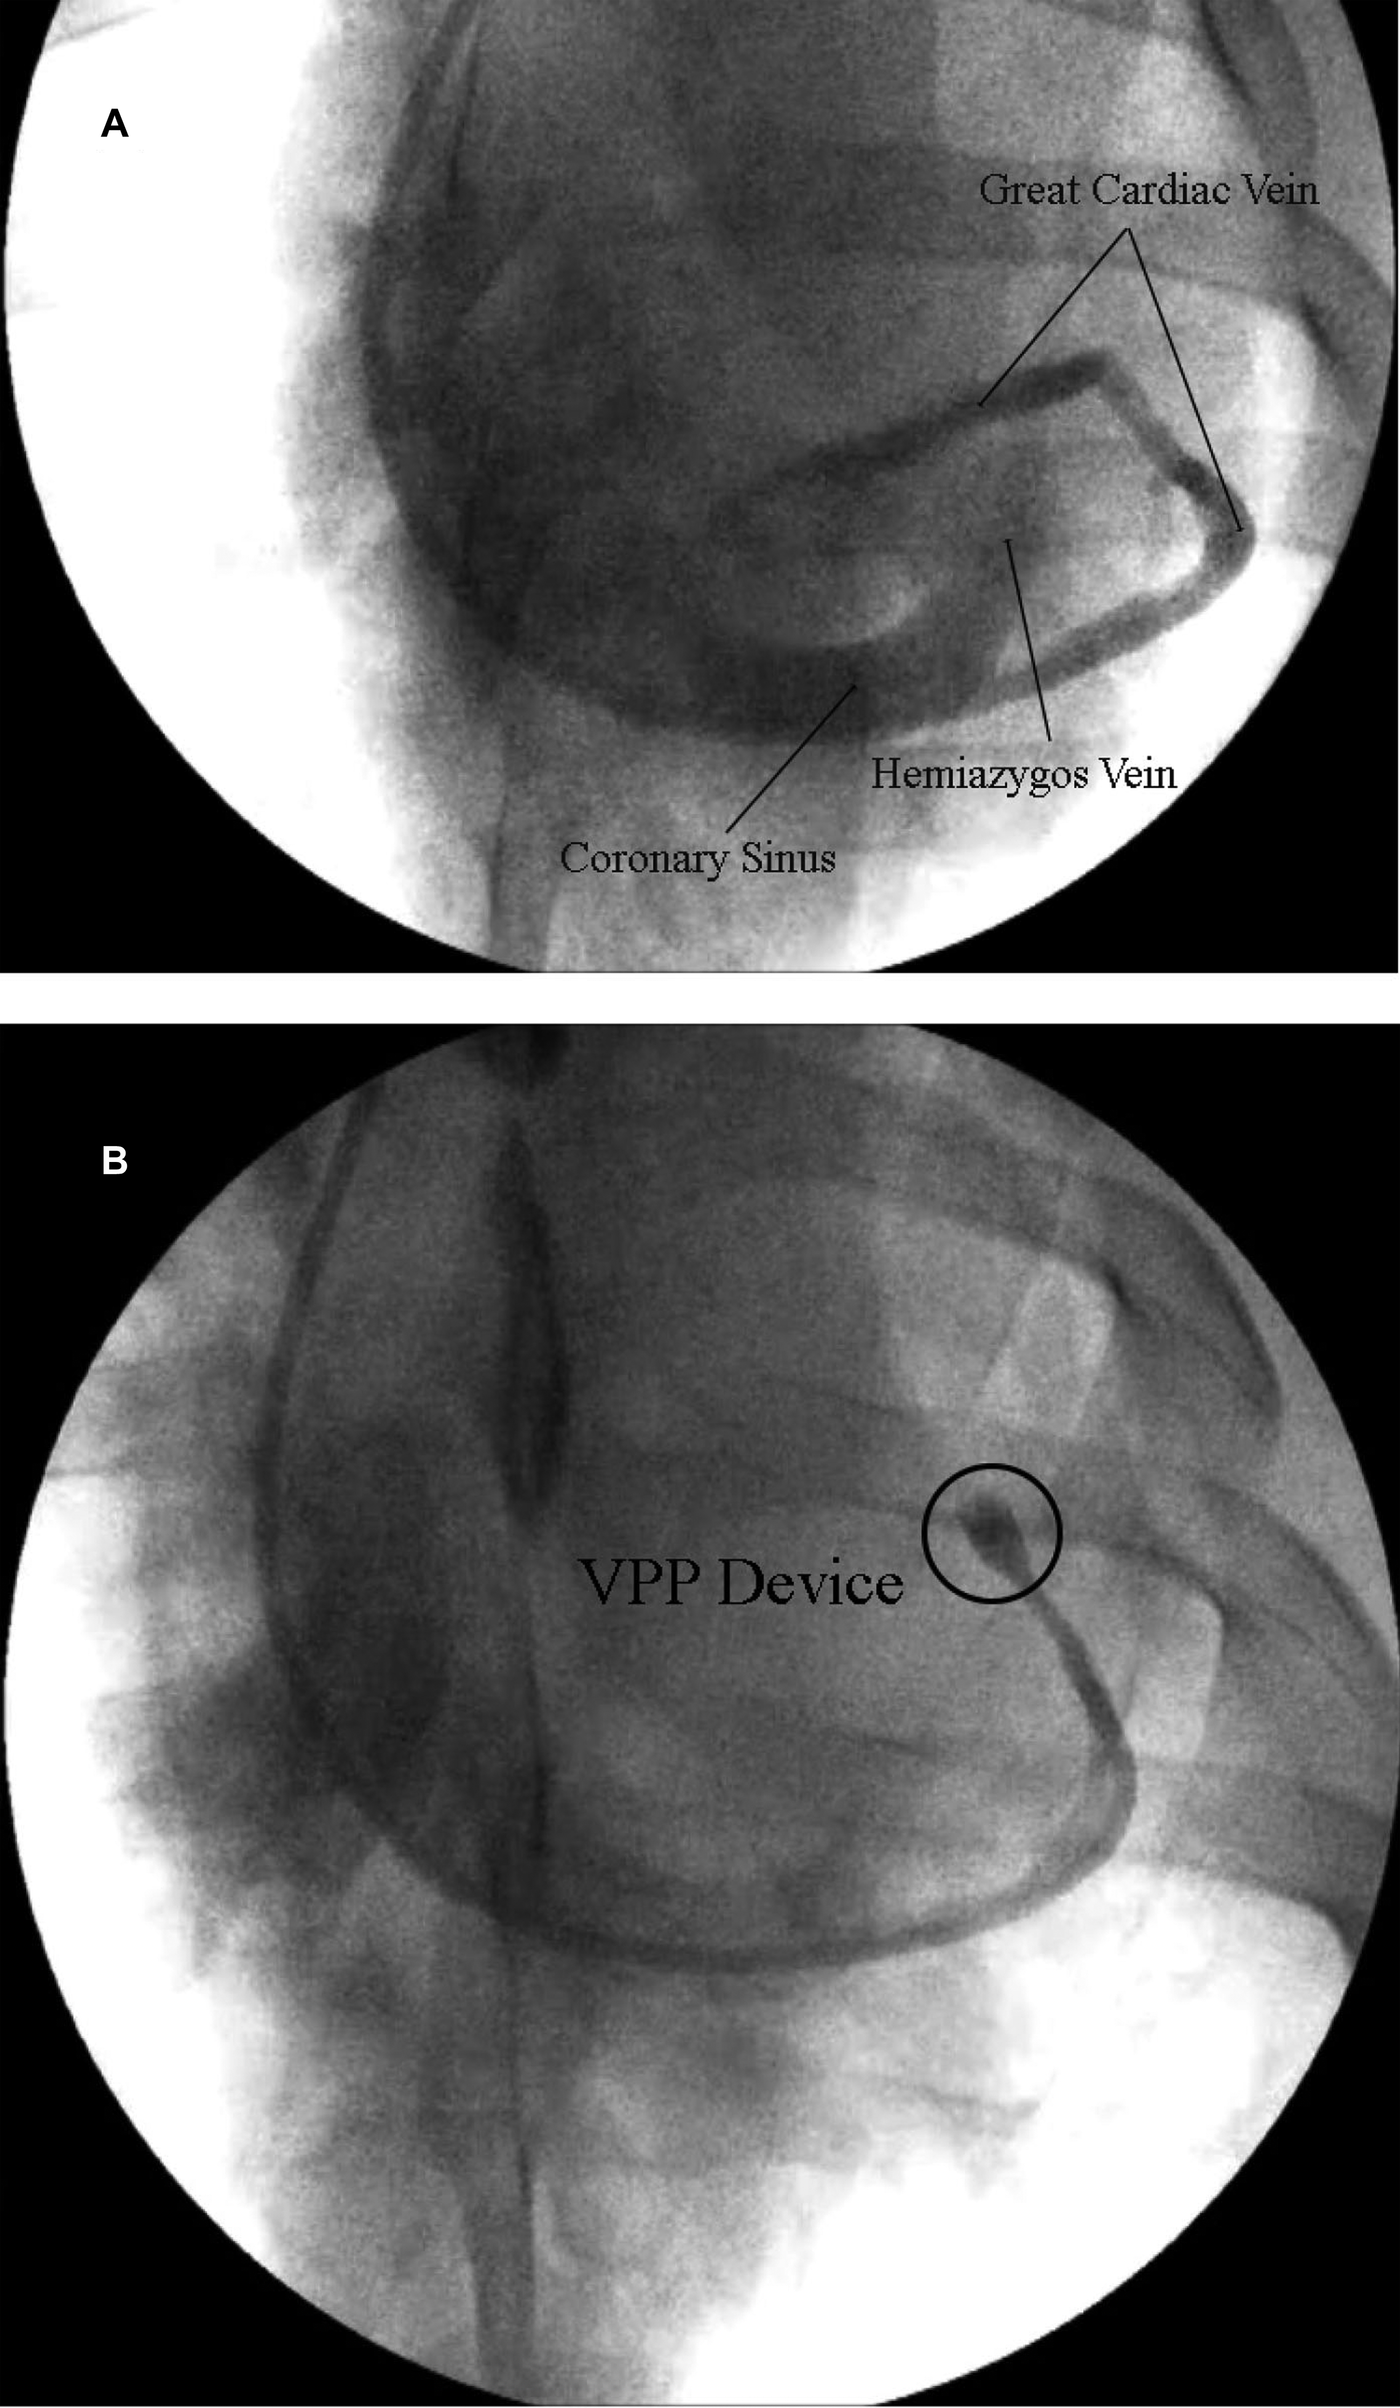

Figure 3

(A) Representative venogram of the coronary sinus, hemiazygos vein and great cardiac vein. (B) Representative venogram of the GCV showing complete occlusion of the vein (cease of contrast) in the interventricular sulcus with the VPP device.

Percutaneous delivery of VPP device

The suture ligation results from the in vivo studies were used to evaluate the efficacy of a novel percutaneous VPP device (Figure 2). The VPP device was deployed in eight animals (Group IB). A 9F introducer sheath was percutaneously inserted into the right jugular vein and a 6F hockey stick catheter was advanced over a hydrophilic 0.035” guidewire into the coronary sinus and the GCV. The guidewire was further advanced towards the apical region and the hockey stick was exchanged with the VPP deployment catheter (a modified Zilver® Vena™ system, Cook Medical, Bloomington, IN). Once in place in the GCV (at the intersection between the anterior longitudinal sulcus and the base of the heart), the VPP device was deployed by pulling back the outer shaft of the catheter. Deployment and occlusion of the vein was confirmed with fluoroscopy, as shown in Figure 3B.